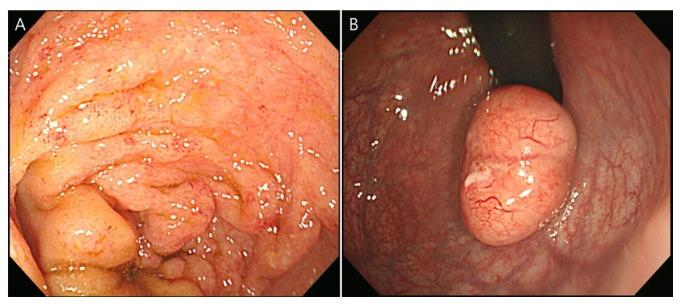

The incidence of rectal neuroendocrine tumor (NET), which is often diagnosed during routine surveillance endoscopy, is increasing. The majority of these tumors are small and asymptomatic, possessing benign features with favorable prognoses. At present, small rectal NETs without high-risk factors are typically treated by local resection, including endoscopic mucosal resection, endoscopic submucosal dissection, or transanal endoscopic microsurgery, with or without additional imaging follow-up by abdominal computed tomography or magnetic resonance imaging. The present study, however, describes a case of a small rectal NET without any known risk factors, which was accompanied by substantial locoregional lymph node metastasis, underscoring the importance of imaging studies for rectal NETs.

直肠神经内分泌肿瘤(NET)的发病率正在上升,这类肿瘤常在常规监测性内镜检查时被诊断出来。这些肿瘤大多体积小且无症状,具有良性特征,预后良好。目前,无高危因素的小直肠NET通常采用局部切除治疗,包括内镜黏膜切除术、内镜黏膜下剥离术或经肛门内镜显微手术,术后可进行或不进行腹部计算机断层扫描或磁共振成像的额外影像学随访。然而,本研究描述了一例无任何已知危险因素的小直肠NET病例,该病例伴有大量局部区域淋巴结转移,强调了直肠NET影像学检查的重要性。